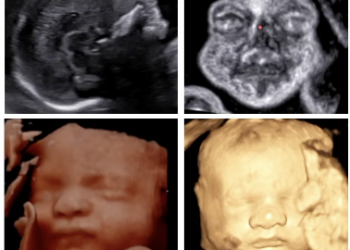

La registrazione dell'evento è fruibile cliccando su VIDEO [pdf-embedder url="https://www.sieog.it/wp-content/uploads/2023/12/webinar-sieog-primo-trimestre-5-12-23-1.pdf" title="webinar sieog primo...

La registrazione dell'evento è fruibile cliccando su Video